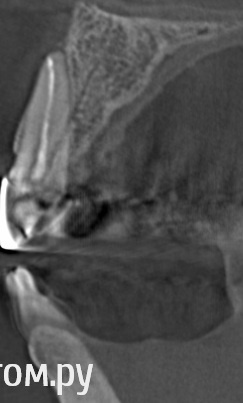

stradalitca Опубликовано 28 мая, 2014 Автор Поделиться Опубликовано 28 мая, 2014 Мужчины, ловите!!!http://s020.radikal.ru/i706/1405/a7/a5d74d5889dd.jpgпотом я немного сдвинула зелёную ось и получилось такhttp://s003.radikal.ru/i202/1405/bd/6606841bbdda.jpgа потом я ещё сдвинула зелёную ось и получилось вот такhttp://s020.radikal.ru/i723/1405/c8/8fe516c63abf.jpgа это зубик 22 в другой проекции( он просто похоже изогнутый, потому и кажется, что пломбровка в сторону идёт)http://s020.radikal.ru/i723/1405/e8/1fe0ffa721ab.jpgну и полная "красота" моего рта))))) мне кажется там ещё под коронками сверху 6, и 7 кариес вовсю идёт. Врач мне посему-то пломбировать не стал, я правда добилась, чтоб он хоть высверлил разъеденную часть. Вообщем он мне по сути цементом коронку залил и прицепил( вместо пломбы оказался цемент)ещё я пришла к выводу, что мне надо ставить пломбы на нижних - 7 справа и 4 слева.http://s43.radikal.ru/i101/1405/3b/411890da6471.jpgчто скажете? Ссылка на комментарий

stradalitca Опубликовано 29 мая, 2014 Автор Поделиться Опубликовано 29 мая, 2014 я никого не хотела обидеть. И тем более Мону.насчёт проткнуть . было так. Она вроде пролечила канал, в конце как будто что-то засунула( ну не знаю, может чтоб поплотнее утрамбовать_ так, что мне показалось, что снизу и до апекса и за апекс ширнуло. Далее она зажигалкой прогрела инструмент и прижгла выход ( или вход?)канала и стала световую пломбу ставить.вот. так всё и было. Вы уже видели новые проекции? по-моему это просто двойка на горизонте проглядывала. Ссылка на комментарий

stradalitca Опубликовано 1 июня, 2014 Автор Поделиться Опубликовано 1 июня, 2014 в начале темы я раместила три фото. на одном, в коричневых тонах, этот зуб( 11) на корне какой-то не такой. в смысле верхушке зуба. Пожалуй, меня это единственное, что смущает. Ссылка на комментарий

Korel Опубликовано 1 июня, 2014 Поделиться Опубликовано 1 июня, 2014 Уважаемые стоматологи, кто-нибудь смотрел последние мои снимки? ( те, где вроде как двойка проглядывает, а не перфорация)? Склоняюсь к перфо. в начале темы я раместила три фото. на одном, в коричневых тонах, этот зуб( 11) на корне какой-то не такой. в смысле верхушке зуба. Пожалуй, меня это единственное, что смущает. Аналогично. я никого не хотела обидеть. И тем более Мону. Мона не обидчивая)) Ссылка на комментарий